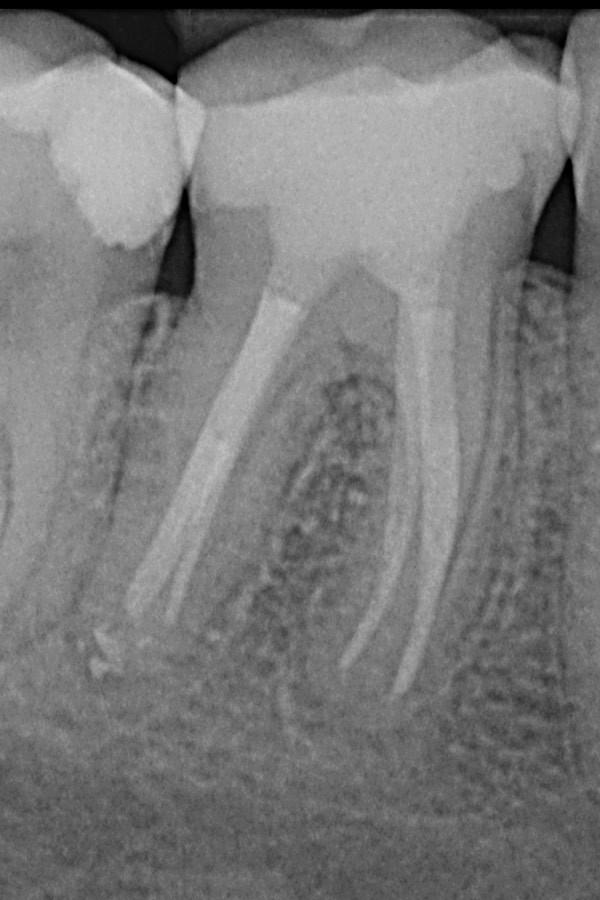

Unvollständige Wurzelfüllungen in zwei Unterkiefer-Prämolaren

Nach Revisionsbehandlung der stark verzweigten Wurzelkanäle

Unterkiefer-Molar mit unvollständiger Wurzelfüllung und Zahnwurzelentzündung

Ausgeheilte Entzündung 1 Jahr später nach Revisionsbehandlung